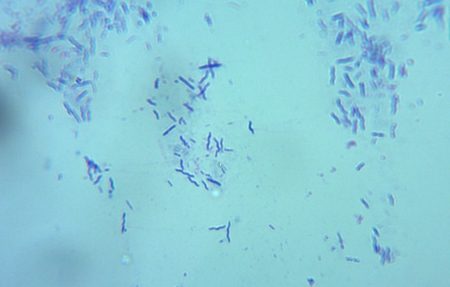

laboratórne vyšetrenie krvi, moču, trusu, cytológia